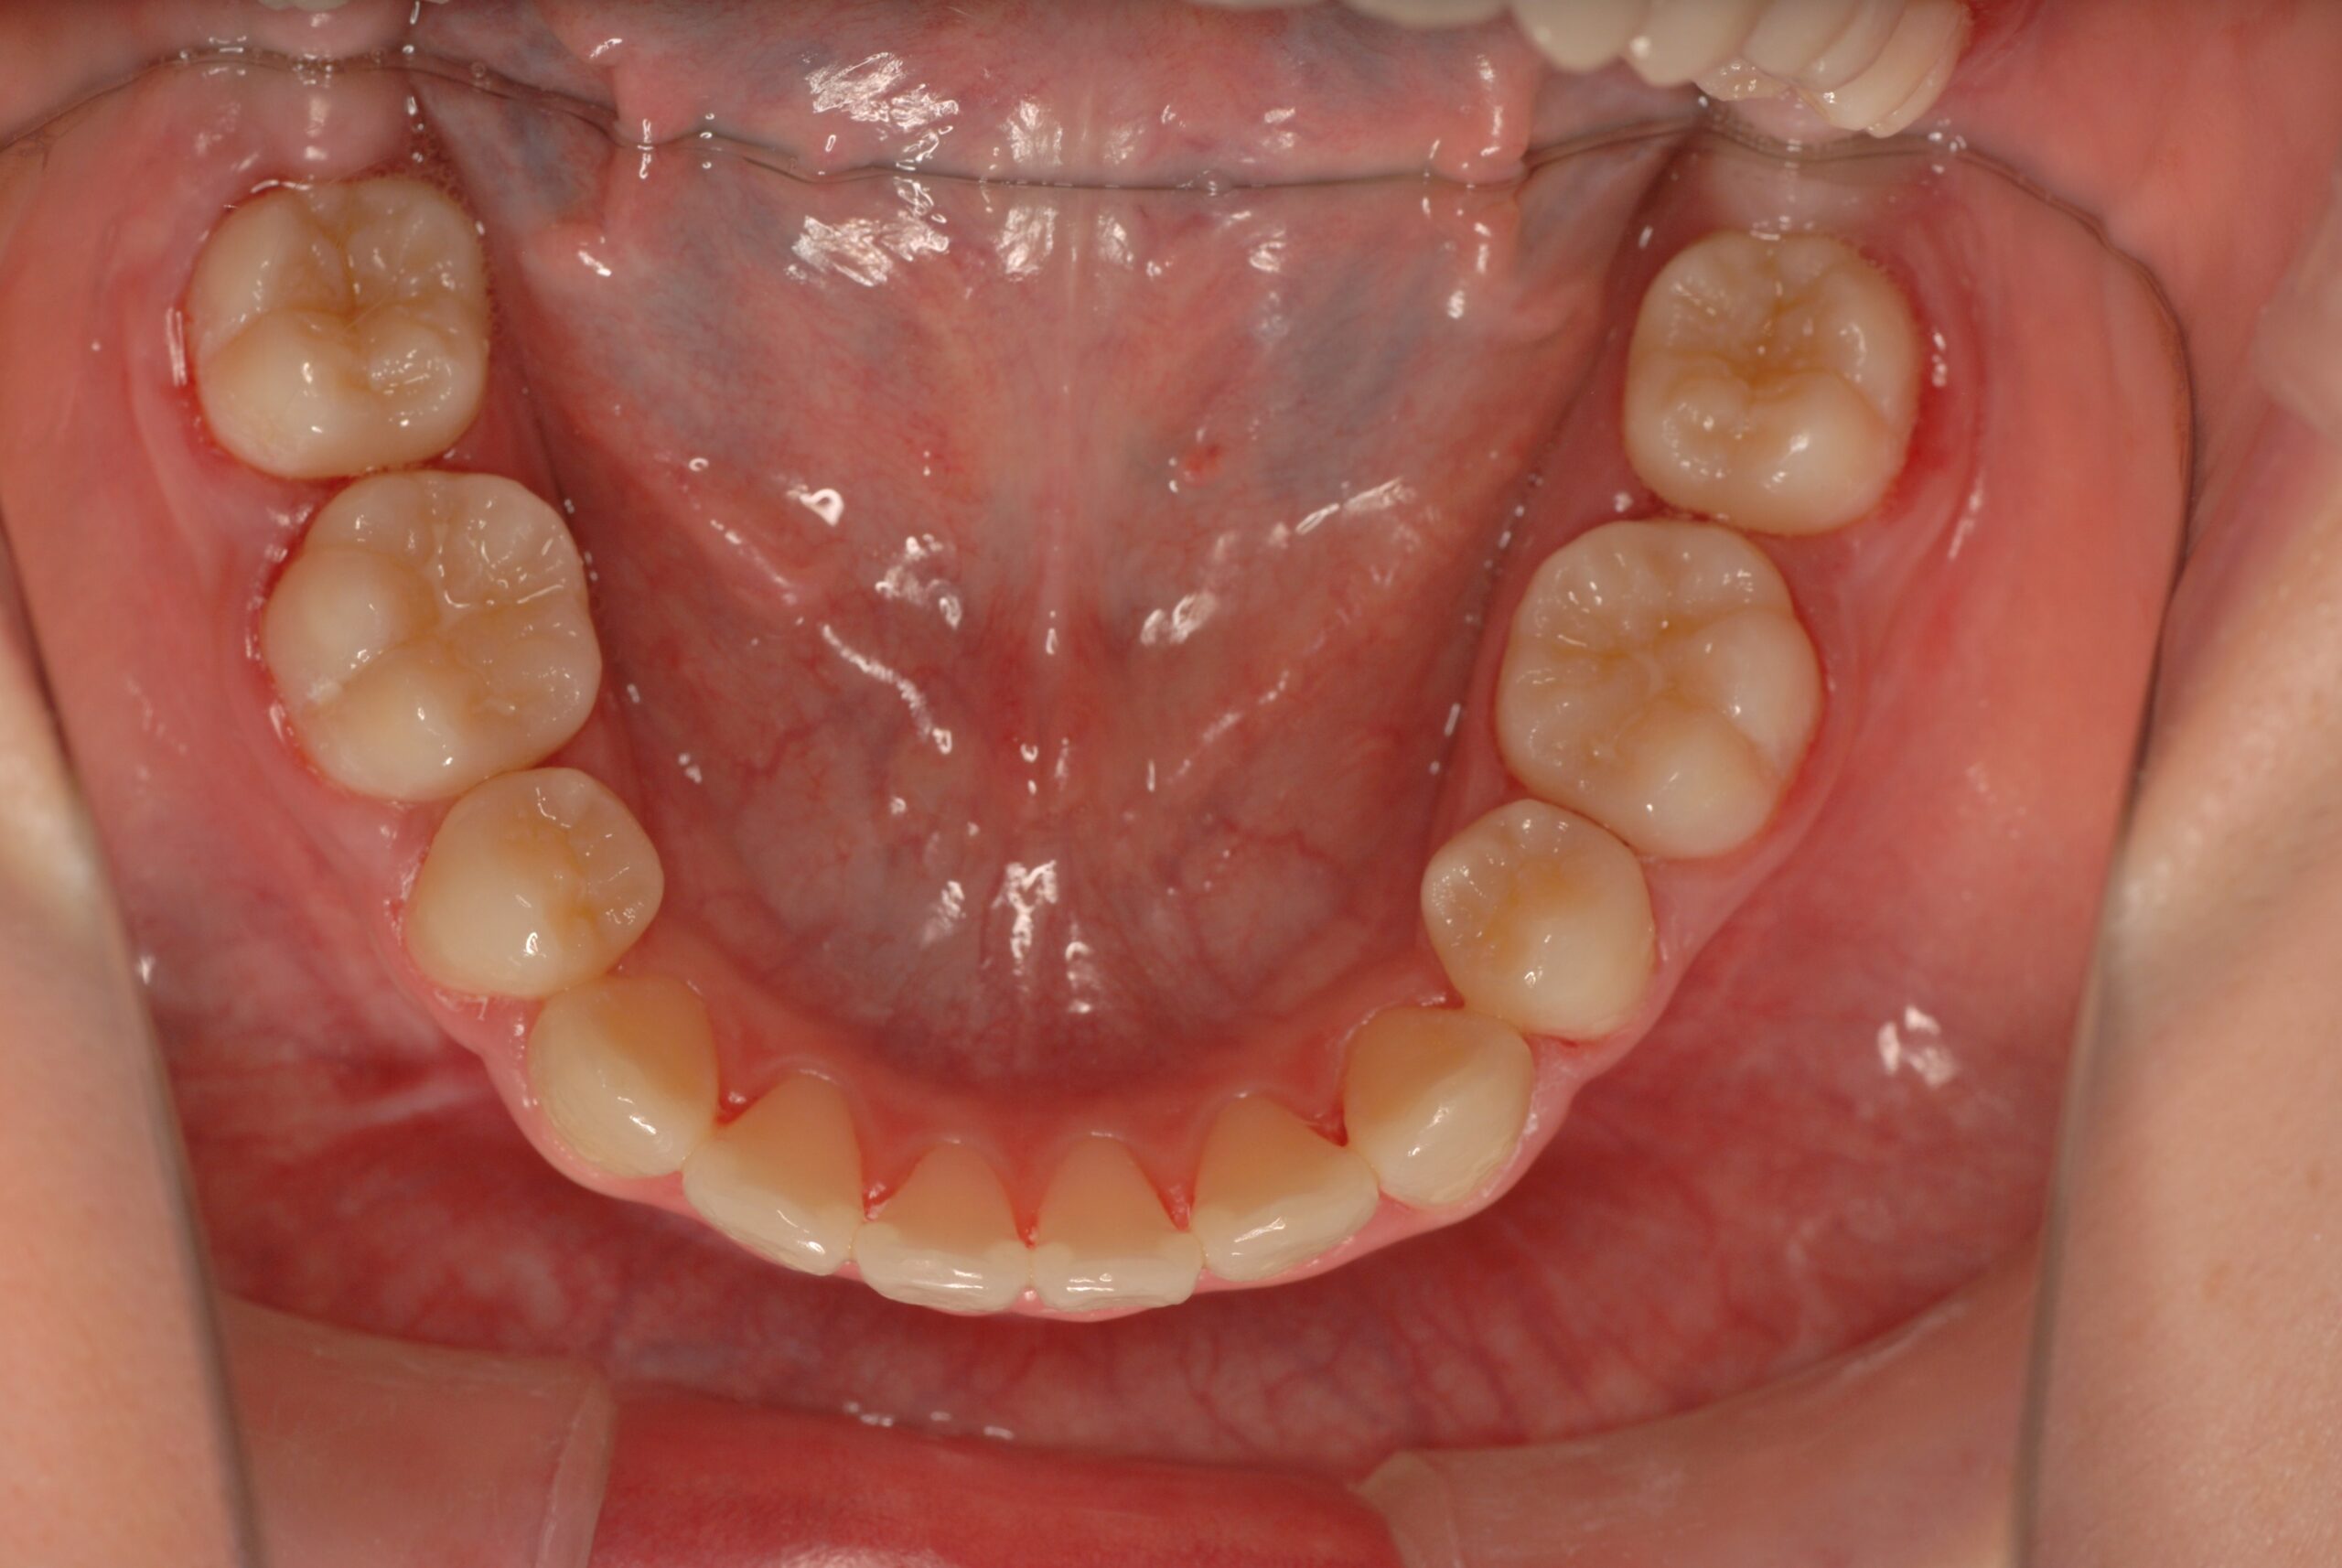

Before

- 診断名、治療内容

- 上顎前突、叢生。 上下顎第一小臼歯を抜歯し、抜歯空隙を利用し、顎外固定装置としてヘッドギヤを併用しながら、上顎前歯を可及的に後退させる。